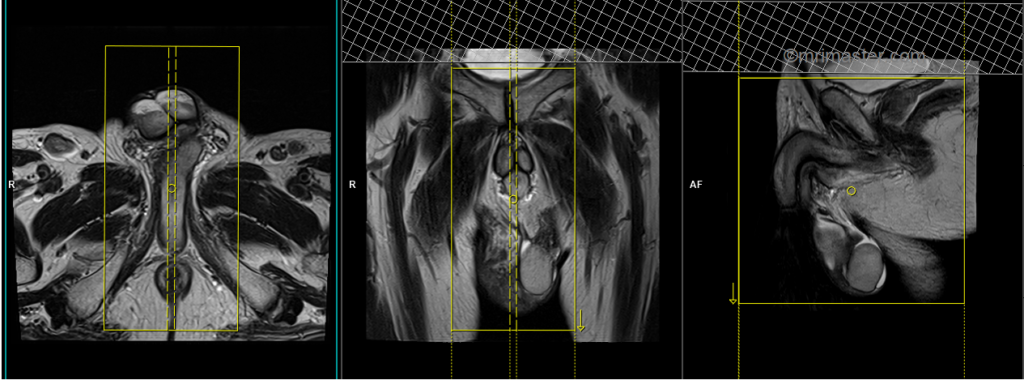

T2 tse sagittal 3mm SFOV

Plan the sagittal slices on the axial plane. Angle the positioning block parallel to the penile shaft and the anal canal. Check the positioning block in the other two planes. An appropriate angle must be given in the coronal plane, parallel to the intrapubic fibrocartilage. Slices must be sufficient to cover the entire scrotum from the right acetabulum to the left acetabulum. The field of view (FOV) must be big enough to cover the scrotum and prostate (normally 200mm-250mm).

Parameters

TR 4000-5000 | TE 100-120 | SLICE 3 MM | FLIP 130-150 | PHASE H>F | MATRIX 320X320 | FOV 250-300 | GAP 10% | NEX(AVRAGE) 3 |

T2 stir axial 3mm SFOV

Plan the axial slices on the sagittal plane; angle the positioning block horizontally across the scrotum (parallel to the penile shaft). Check the positioning block in the other two planes. Ensure an appropriate angle is given in the coronal plane (horizontally across the testis). The slices must be sufficient to cover the scrotum from the prostate down to 1 cm below the scrotum.